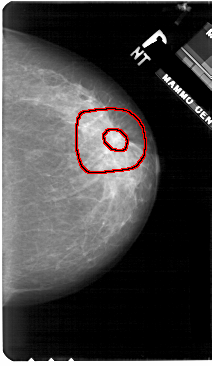

A_1906_1.RIGHT_MLO

FILE: A_1906_1.RIGHT_MLO.OVERLAY

TOTAL_ABNORMALITIES 1

ABNORMALITY 1

LESION_TYPE MASS SHAPE ARCHITECTURAL_DISTORTION MARGINS SPICULATED

ASSESSMENT 5

SUBTLETY 4

PATHOLOGY MALIGNANT

TOTAL_OUTLINES 2

BOUNDARY

CORE